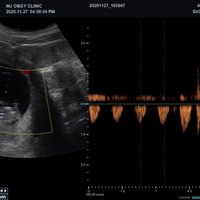

Mit dem X-CUBE 90 beginnt ALPINION eine neue Generation an Farbdopplersystemen, die X- CUBE Serie. Mit Bildverarbeitungstechnologien eines Premiumsystems und neuen Breitband- Schallköpfen mit X + Crystal Signature™ Technologie wartet das neue X-CUBE 90 auf.

Neben der hohen Bildqualität liegt ein weiterer Fokus auf der Vereinfachung und der Anpassung der Bedienung des Ultraschallgeräts. Individuell programmierbare Workflows und ein erweitertes Spektrum an automatisierten Messungen ermöglichen ein schnelleres und genaueres Arbeiten in jeder Situation.

eXpanded Capability

Das X-CUBE 90 bietet modernste Technologien für eine objektive und akkurate Diagnose. Intelligente klinische Module heben das System auf ein neues diagnostisches Niveau. Es erweitert Ihre Fähigkeiten und die Bandbreite Ihrer Möglichkeiten. Dazu gehören Module wie MicroView, point Shear Wave Elastographie (pSWE), oder auch die Kontrastmittelsonographie.

• SVC1-8H (1-8 MHz) für Ultraschalluntersuchungen in Bereichen Abdomen, Geburtshilfe, Gynäkologie, Urologie, Pädiatrie, EM